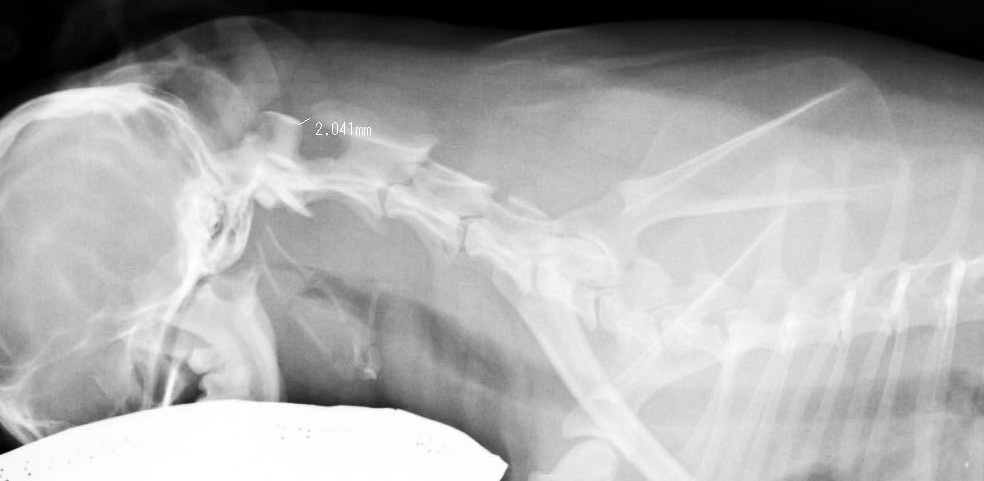

トイプードル 4.5才 メス BW3.3kg

左前足を上げている

抱き上げようとしたら痛がった

首に力入っている 下に動かさない

触ると痛がる

軽度の冠軸亜脱臼